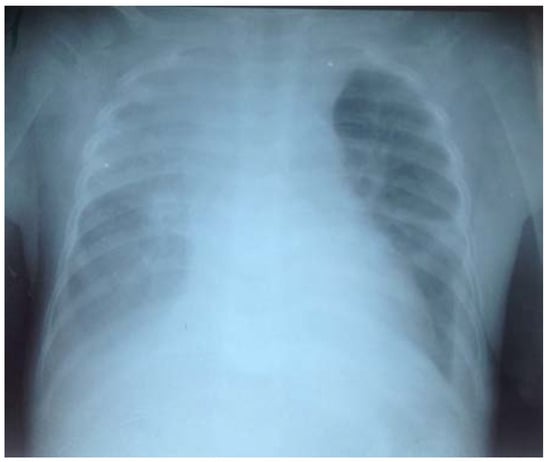

Laboratory tests showed: white blood cells at 12,800 per μL with leukocytes differential of 23% lymphocytes, 62% neutrophils, 7% monocytes, 7% eosinophils, 1% basophils; red blood cells 2,840,000 per μL, hemoglobin 6.9 per μL, hematocrit 21%; and 196,000 platelets per μL. HIV serology was negative, with negative HBsAg, negative anti-HCV, negative Ziehl Neelsen stain and negative M. tuberculosis PCR from gastric aspirate, negative blood film for malaria, negative bacteriological urinalysis, albumin 2.1 mg/dL, negative proteinuria and negative glycosuria. His chest X-ray showed a base reticular opacity on the right field (Figure 1).

Figure 1.

Chest X-ray at admission. Note a reticular opacity in the base of the right field.